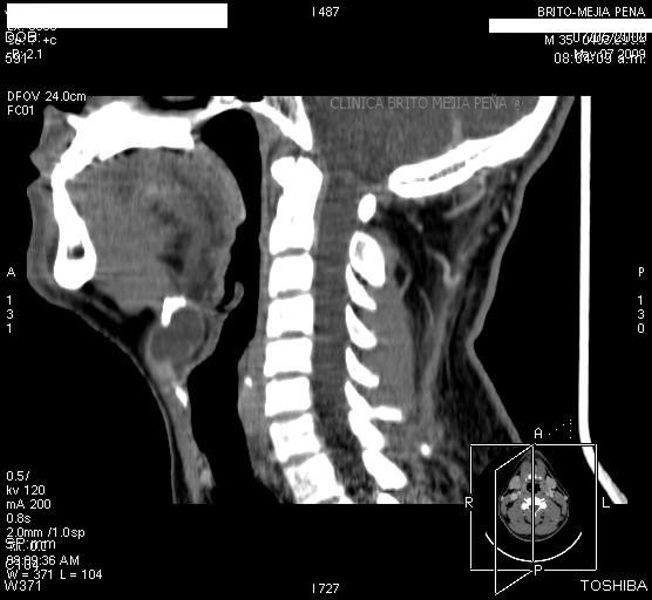

Cabeza y Cuello 2

Envíado por BMP Imágenes Diagnósticas

BMP Imágenes Diagnósticas